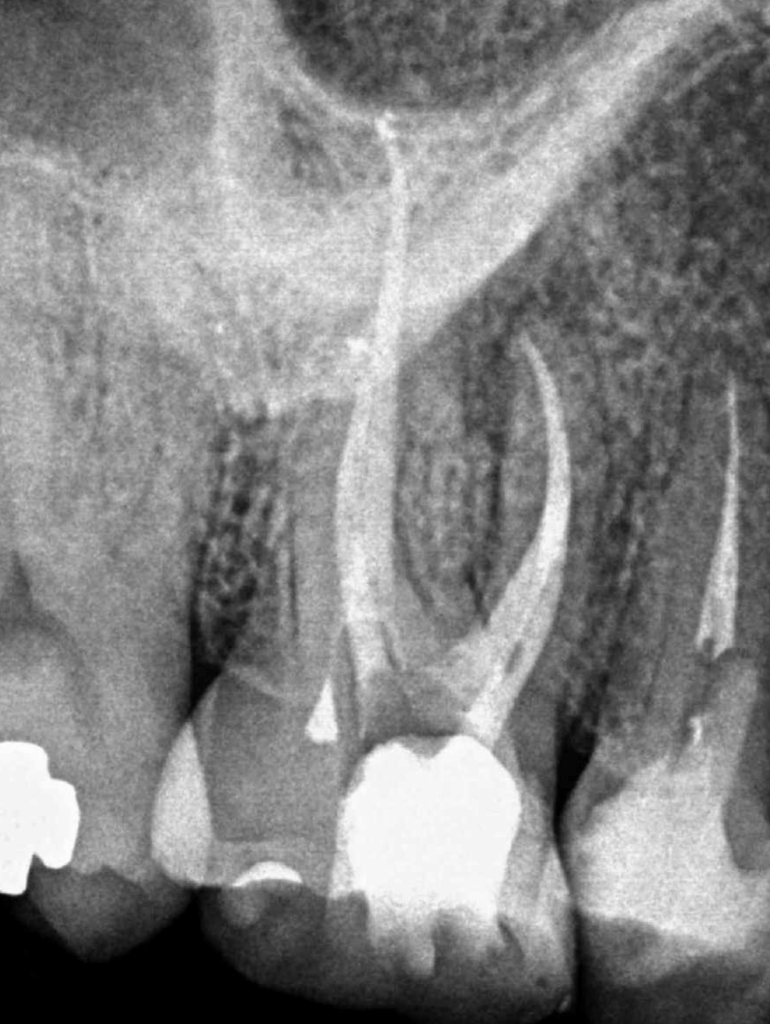

Reco preendo + 4 conductos molar superior